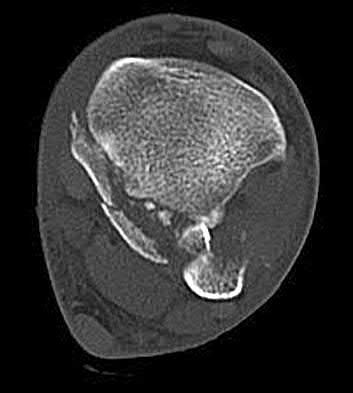

A 15-year-old boy presents with a permeative lytic lesion in the femoral diaphysis with aggressive periosteal reaction ('onion skinning'). Biopsy reveals uniform small round blue cells. Cytogenetic analysis of this tumor will most likely demonstrate which of the following translocations?

Explanation

The clinical and radiographic description is classic for Ewing sarcoma. The characteristic cytogenetic abnormality is a balanced translocation t(11;22)(q24;q12), which fuses the EWS gene on chromosome 22 with the FLI1 gene on chromosome 11. This is seen in approximately 85-90% of Ewing sarcomas. t(9;22) is the Philadelphia chromosome (CML), t(X;18) is seen in synovial sarcoma, t(2;13) in alveolar rhabdomyosarcoma, and t(12;16) in myxoid liposarcoma.